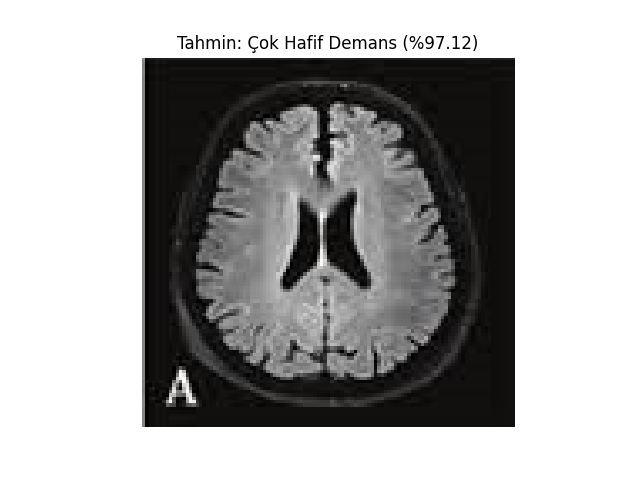

def show_image_with_prediction(image_path, prediction, confidence, class_names):

image = Image.open(image_path)

plt.imshow(image)

plt.title(f"Tahmin: {class_names[prediction]} (%{confidence * 100:.2f})")

plt.axis('off')

plt.show()

test_image_path = 'MRI/veya/fMRI/görüntüsü'

prediction, confidence = predict(test_image_path, model, transform)

print(f'Tahmin: {class_names[prediction]} (%{confidence * 100})')

show_image_with_prediction(test_image_path, prediction, confidence, class_names)Vbai Modelleri;